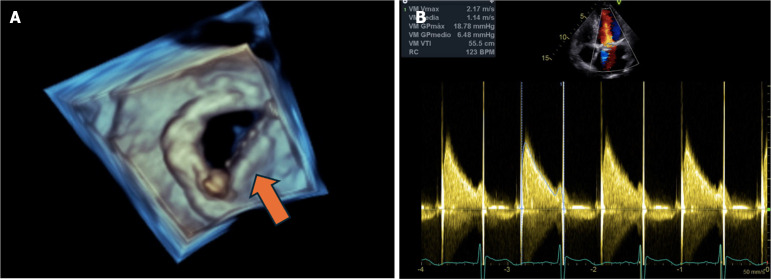

Case summary: We present a case of a 71-year-old female patient with a history of mitral valve replacement and warfarin anti-coagulation therapy. She was admitted to the intensive care unit due to spontaneously reperfused ischemic stroke of probable cardioembolic etiology. A dysfunctional mitral prosthesis was identified due to malfunction of one of the fixed discs. Furthermore, a possible microthrombotic lesion was suspected. Therefore, systemic thrombolysis was performed with subsequent normalization of mitral disc opening and closing.